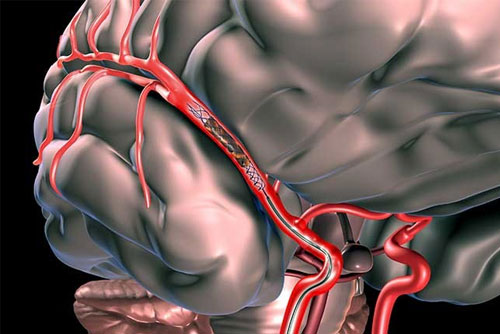

Neuro Intervention

Stroke Management

Carotid Stenting

Intracranial Stenting

Mechanical Thrombectomy Stroke